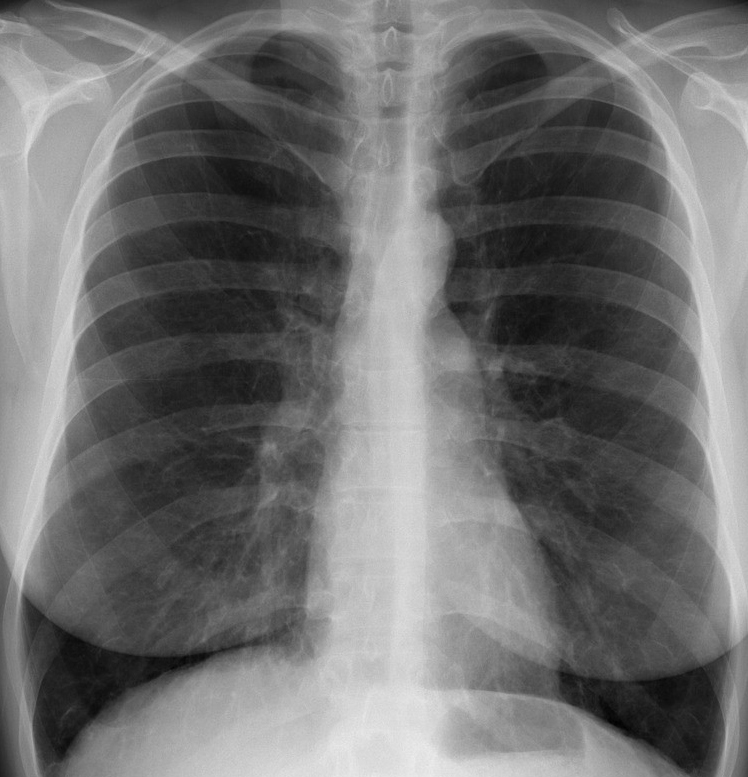

Figure 6 presents image examples for each class retrieved from the RYDLS-20 database. It is worth to mentioning that we have no further information concerning the CXR images with regarding the CXR machine used to take the image, as well as the origin, age and ethnicity of the people whose these images belong to.

Refer to caption

(a) Normal.

Figure 6: RYDLS-20 image samples.